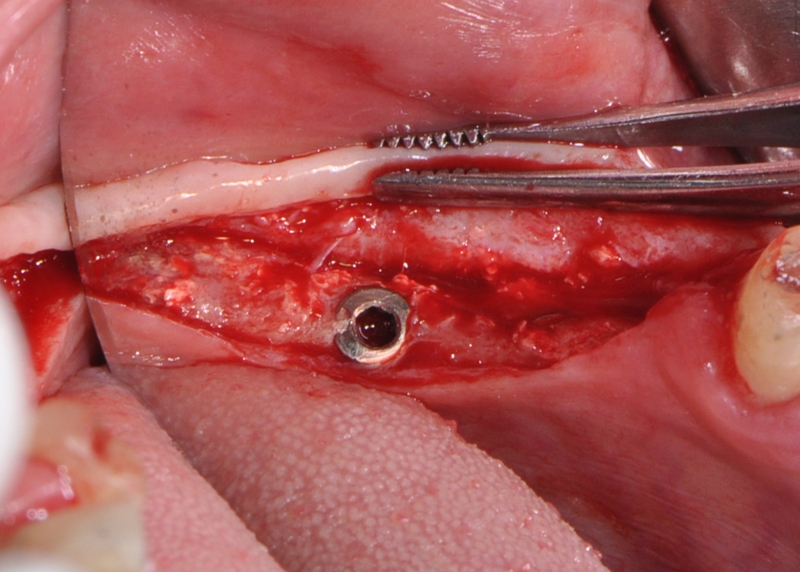

Implant insertion in atrophic alveolar ridge